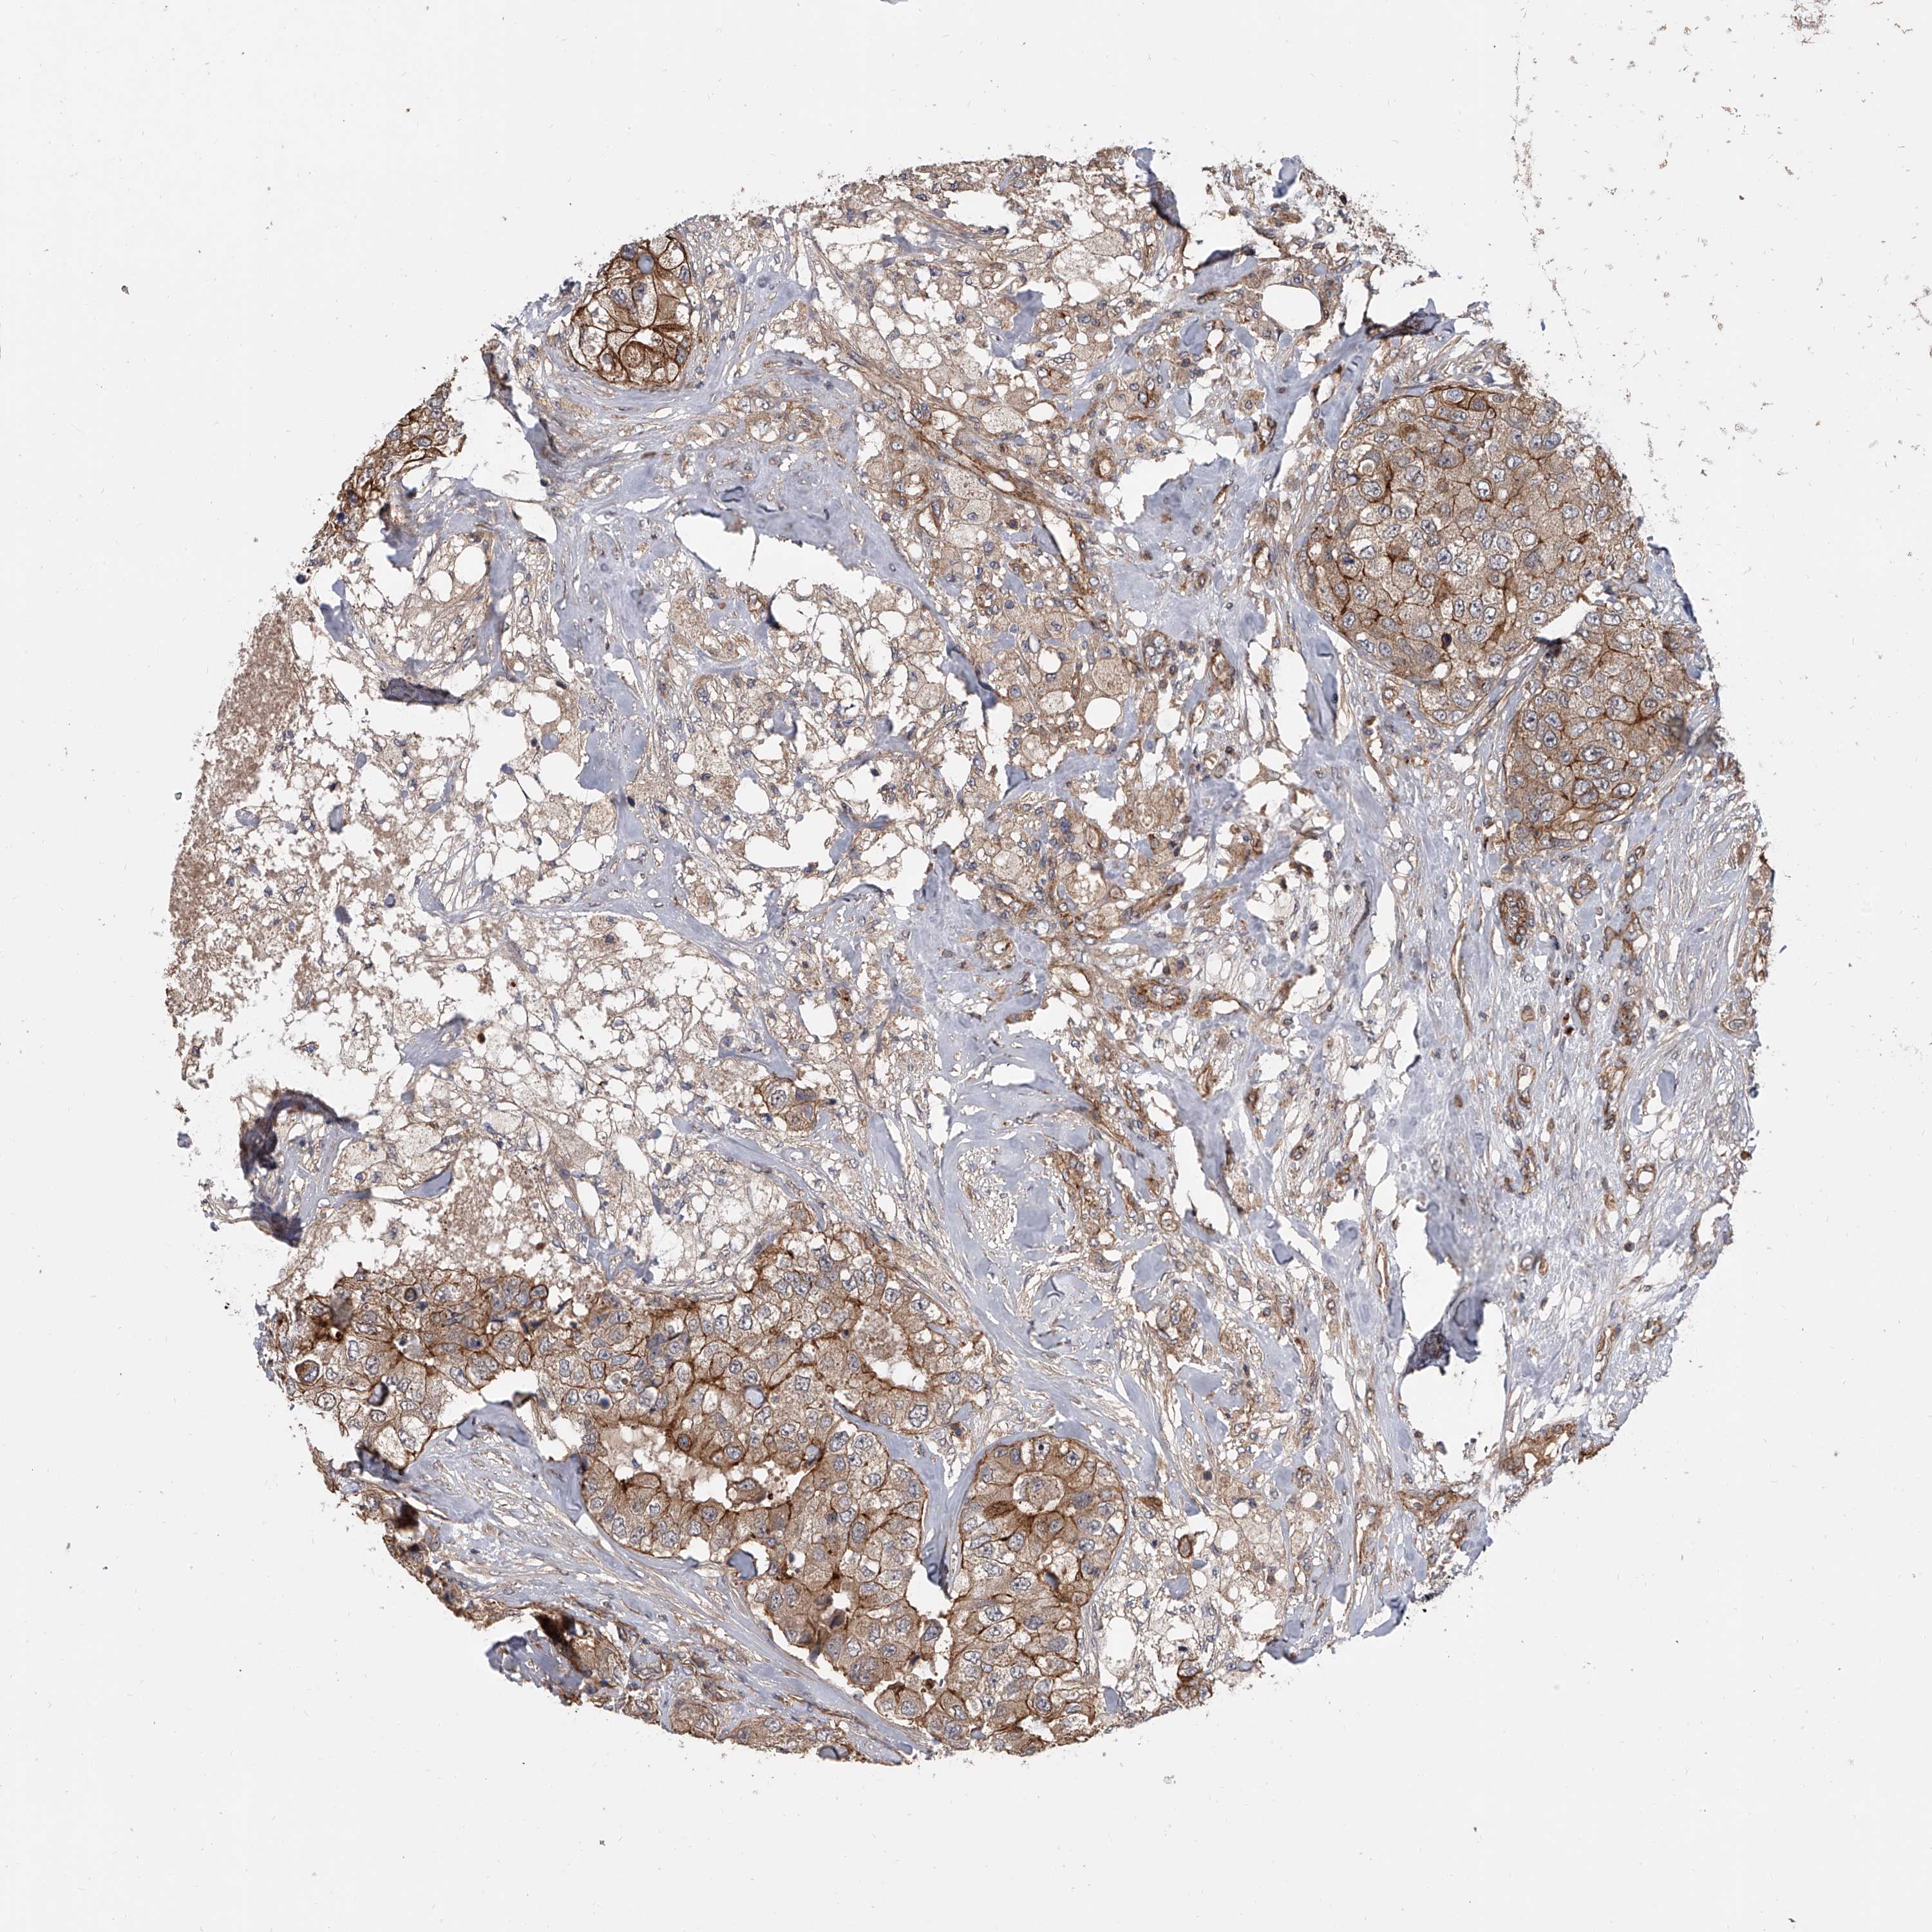

CANCER BREAST CANCER Show tissue menu

BRCA TCGA BRCA VALIDATION PROTEIN EXPRESSION